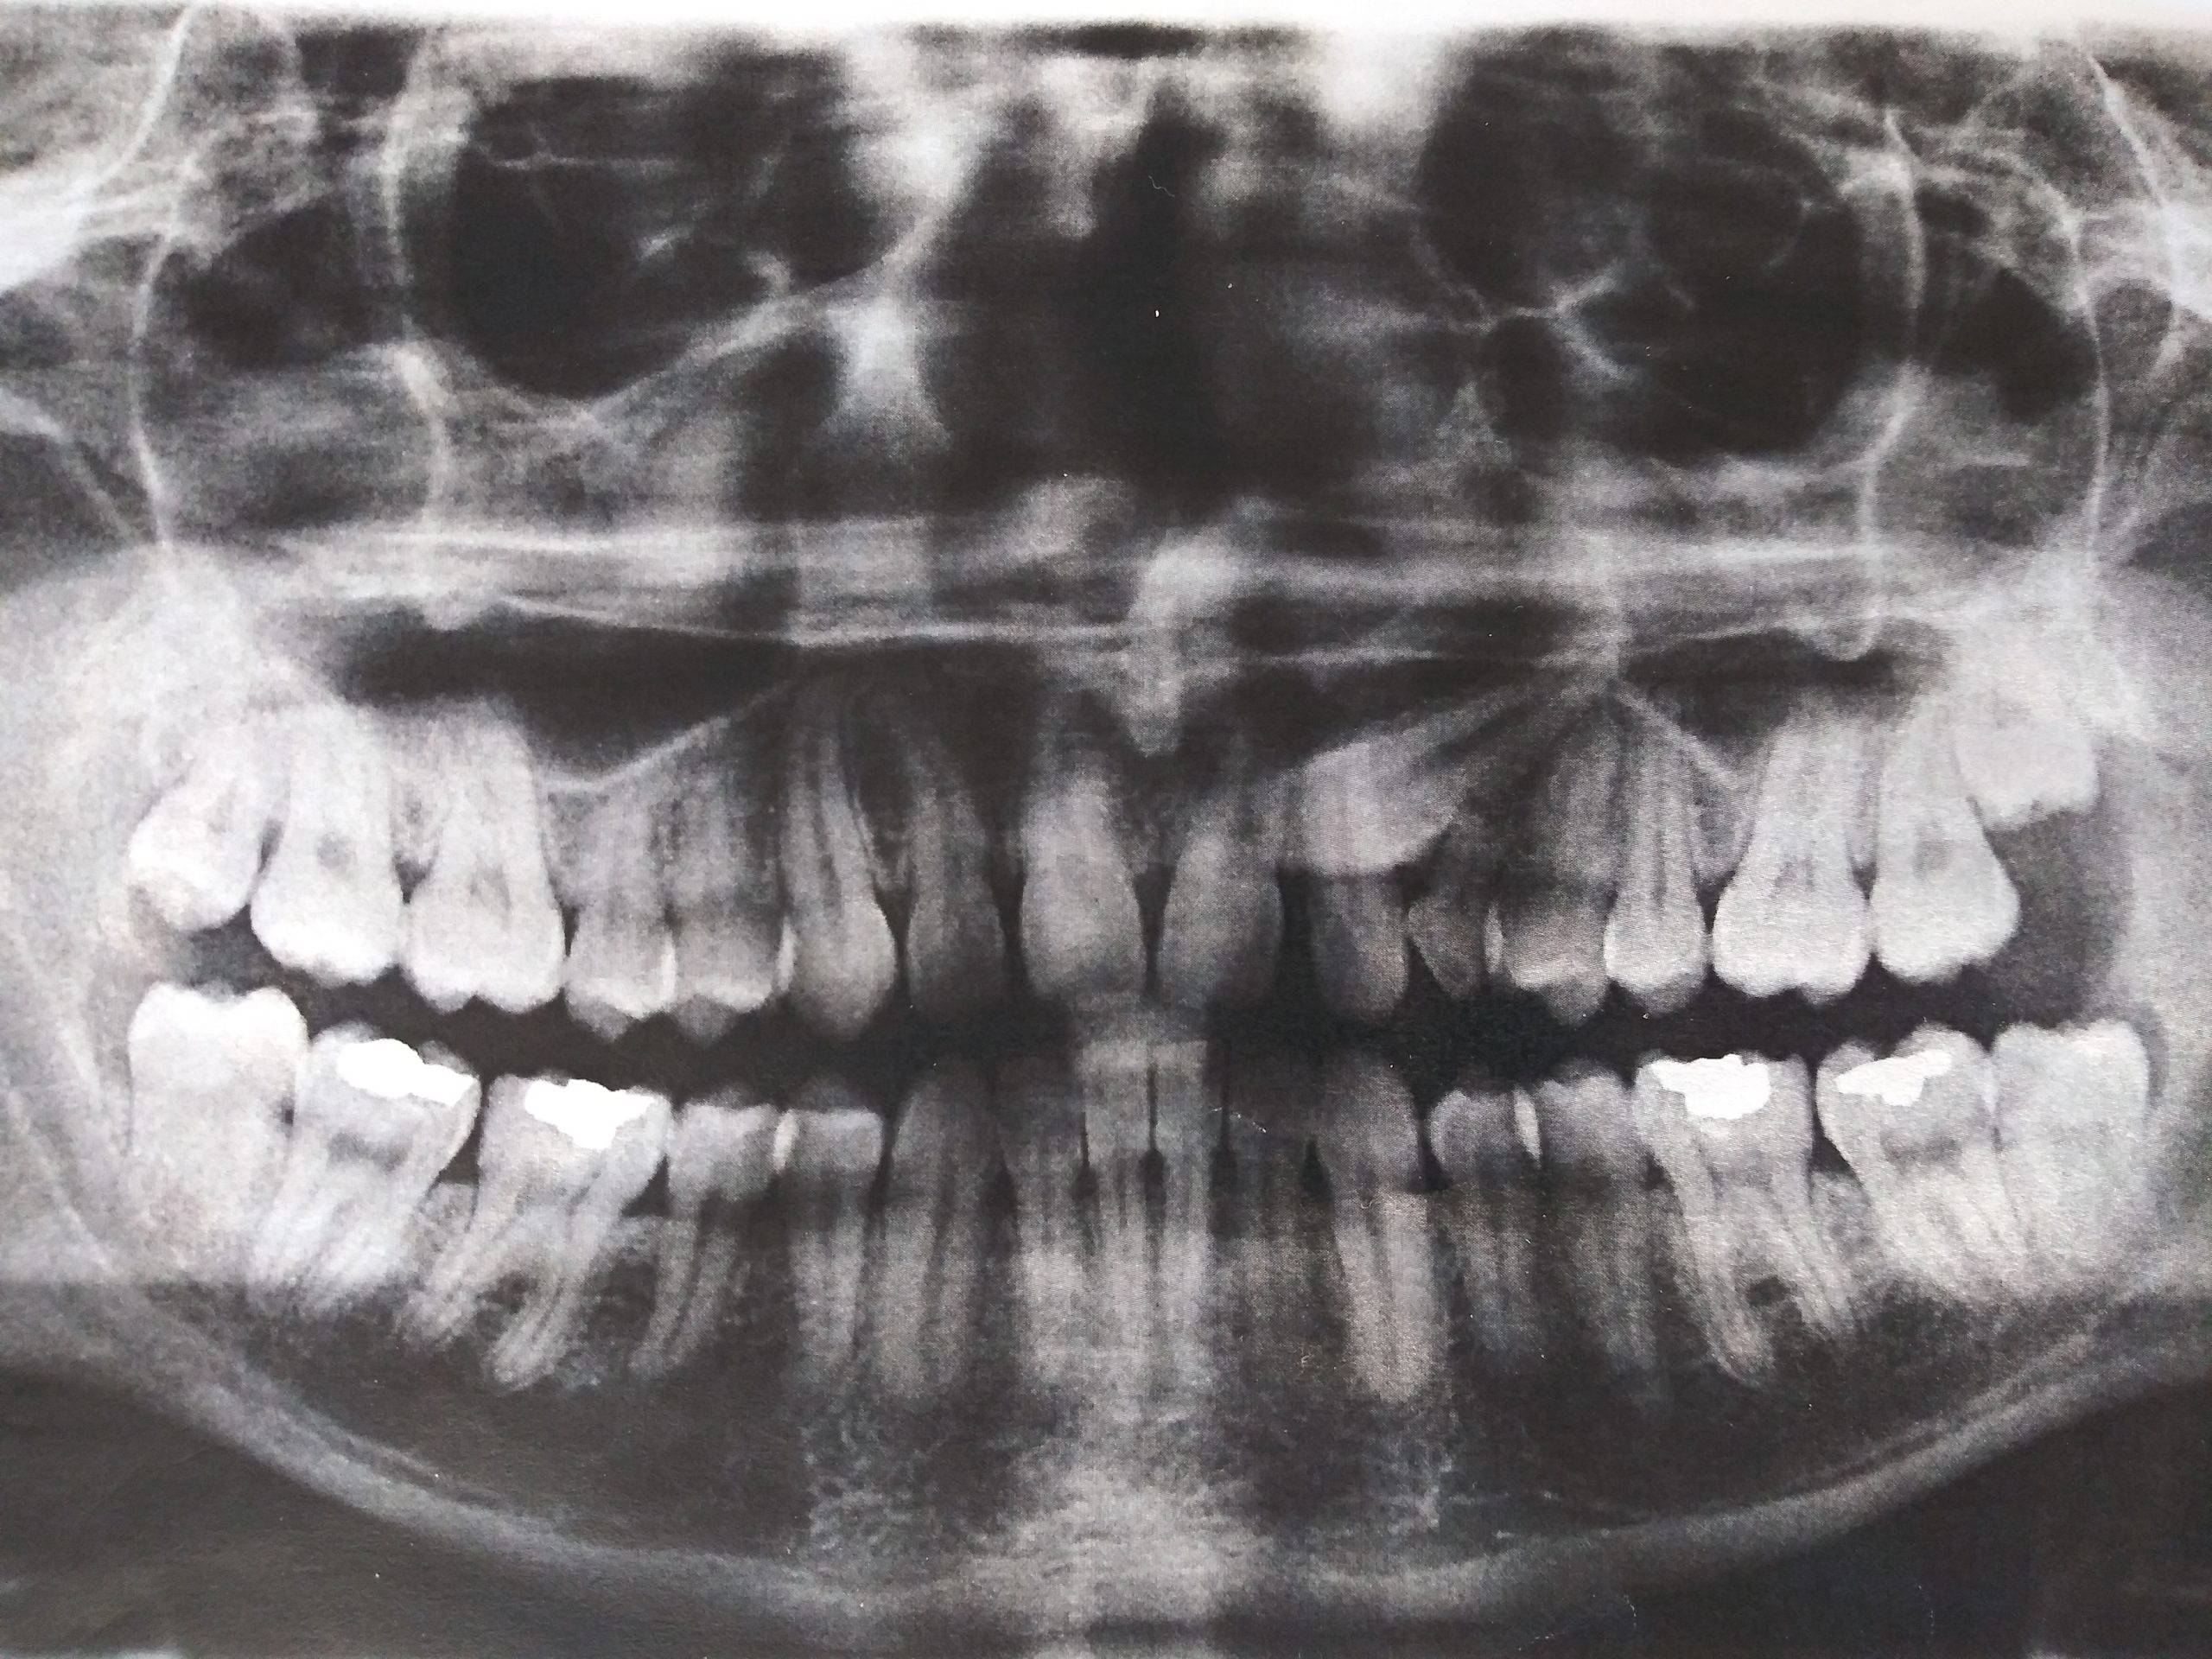

Case #1 and case #2: canine #13 was impacted and ankylosed. Case #3: Agenesis of 2 permanent canines #13 and #23.

Cases #1 and #2 each had their canine #13 impacted and ankylosed, that is fused to the bone. It was thus impossible to proceed with their orthodontic traction. The removal of the impacted tooth was necessary. The patients were told that the removal of 3 premolars (#24, #34 and #44 for case #1 and #24, #35 and #45 for case #2) would be necessary to obtain an ideal occlusion. The Xs represent the spot where the canines would be if they existed. The first premolars #14 and #24 are identified. The replacement of canines by first premolars allows the patient to obtain an acceptable esthetic and functional result.

Dentigerous or follicular cyst. The 13 indicates the permanent canine. The “C” indicates the primary canine. The dotted white line indicates the extent of the cyst.

A chronic apical lesion of the primary canine facilitated the development of a follicular cyst and the exaggerated movement of the permanent tooth #13.

This exaggerated upward and forward movement of the impacted canine makes the de-impaction treatment more difficult and longer.

Incisors can suffer from resorption of their root. Note that the central incisors lost at least 50% of their length because of the impacted canines. Figuratively, we could say that there was a collision between the canine and the root of the incisor and the root “disappeared”.

In that case, we decided to extract the impacted canines, because it would have been impossible to perform the traction of these canines without causing more damage to the roots of the incisors.

This patient was lucky, because sometimes, one or more incisors need to be extracted like in this other case shown on the right.